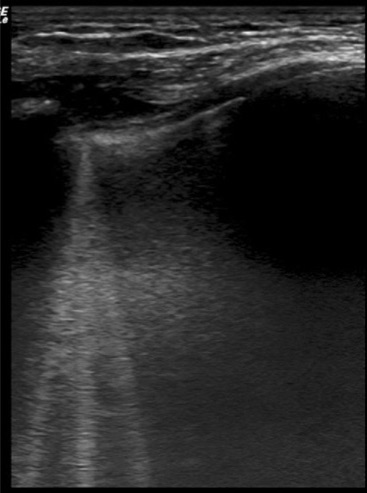

The main findings are the comet tails. They are described as hyperechoic, with a narrow start from the pleuritic line, extending deeply in the lungs. It has been extensively studied for cardiogenic pulmonary edema and it is a sign of fluid accumulation in the lungs.

This is a good example of comet tails:

(Source : Wimalasena et al, Wilderness Environ Med)